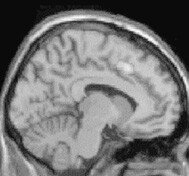

왕따 당하면 대뇌가 고통스럽다

한사람을 집단적으로 따돌리는 이른바 ‘왕따’ 현상이 사회적 문제가 된 지 오래다. 국무총리산하 청소년보호위원회가 8월20일 발표한 자료에 따르면 우리나라 학생 10명 중 1명이 학교에서 왕따를 당하고 있는 것으로 나타났다. 이러한 …